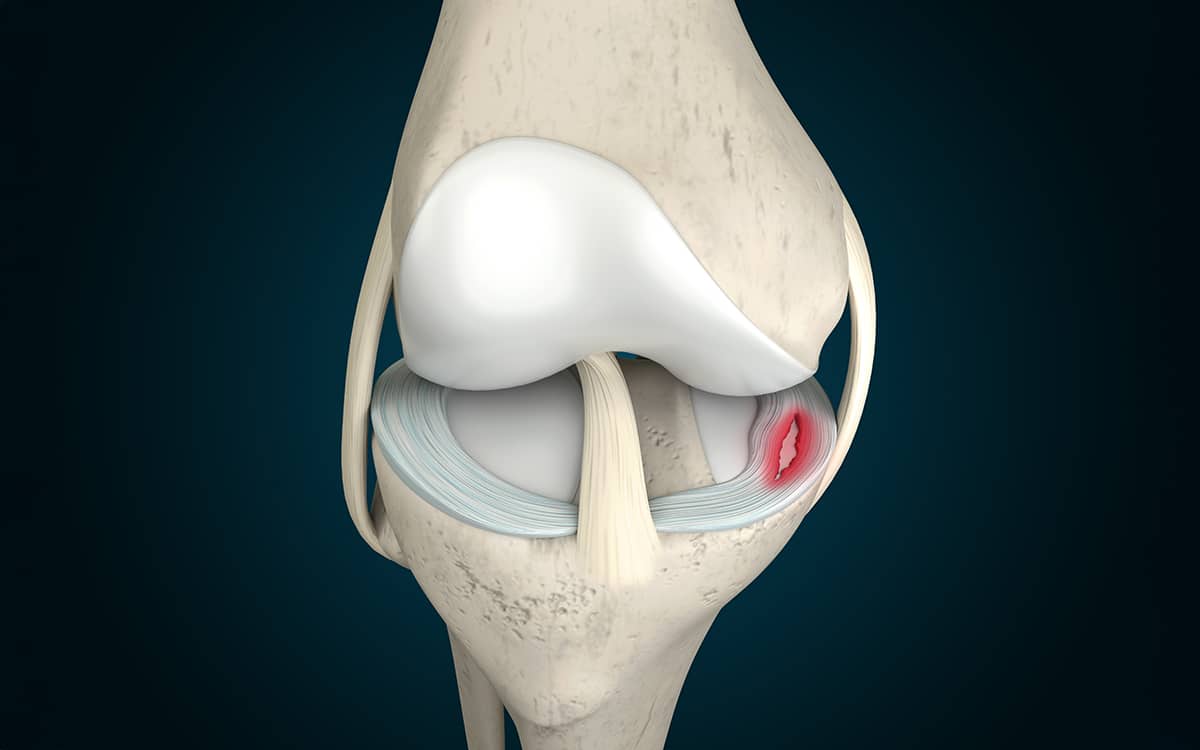

مینیسک زانو یک ساختار غضروفی به شکل هلالی است که بین استخوان ران و استخوان ساق قرار میگیرد. هر زانو دارای دو مینیسک (داخلی و خارجی) است که نقش مهمی در جذب فشار، توزیع یکنواخت وزن و پایداری مفصل ایفا میکنند. این بافتها به نوعی ضربهگیر طبیعی زانو محسوب میشوند و مانع از سایش استخوانها بر روی یکدیگر میشوند.

بدون وجود مینیسک، فشار وزن بدن مستقیماً به سطح مفصلی وارد میشود و احتمال بروز آرتروز و دردهای مزمن بالا میرود. به همین دلیل، آسیبدیدگی یا پارگی مینیسک زانو میتواند مشکلات زیادی ایجاد کند و نیاز به درمان فوری دارد.

انواع پارگی مینیسک زانو

پارگیهای مینیسک بسته به شکل و محل آنها به دستههای مختلفی تقسیم میشوند:

پارگی طولی: در امتداد لبه مینیسک ایجاد میشود.

پارگی افقی: مینیسک را به دو لایه تقسیم میکند.

پارگی شعاعی: از مرکز به سمت لبه مینیسک حرکت میکند.

پارگی پیچیده: ترکیبی از چند نوع پارگی.

پارگی دستهسطل: بخشی از مینیسک جابهجا شده و موجب قفل شدن زانو میشود.

هر نوع پارگی میتواند درمان خاص خود را داشته باشد که بسته به شدت آسیب و شرایط بیمار انتخاب میشود.